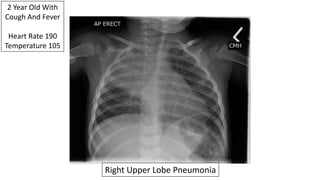

2 Year Old With

Cough And Fever

Heart Rate 190

Temperature 105

Right Upper Lobe Pneumonia